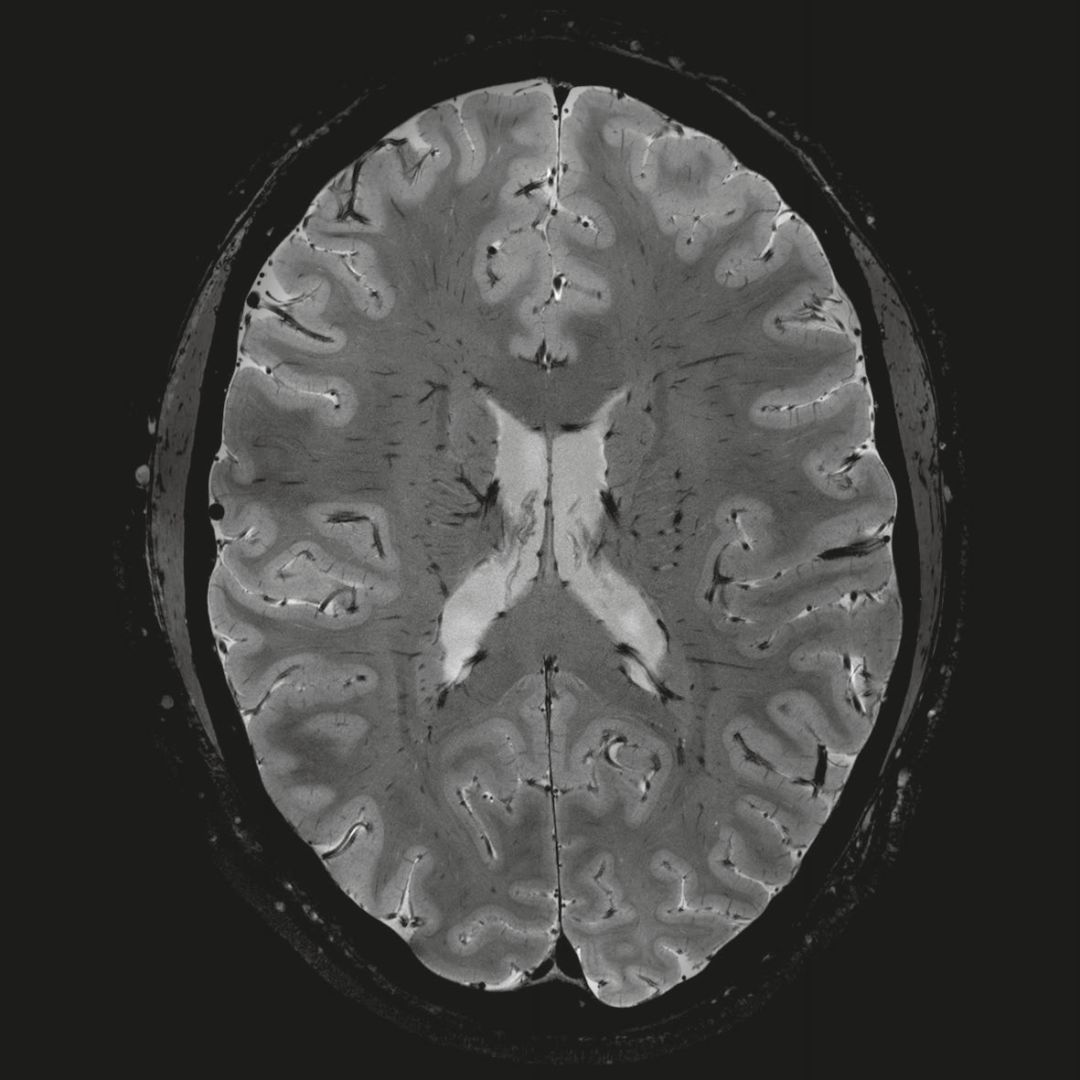

但近年來(lái),西門子與科研機(jī)構(gòu)共同研究發(fā)現(xiàn),7T提供了數(shù)倍于傳統(tǒng)3T磁共振的信噪比和空間分辨率,在神經(jīng)、血管、腫瘤、骨關(guān)節(jié)等多個(gè)方面都會(huì)帶來(lái)全新的突破性進(jìn)展。尤其是在目前常規(guī)影像設(shè)備難以診斷的神經(jīng)退行性疾病如阿茲海默氏病、帕金森病等疾病的發(fā)病機(jī)理、早期診斷、治療方案確定以及治療效果評(píng)估上,有著極大的潛力。

MAGNETOM Terra在業(yè)界首次實(shí)現(xiàn)了兩倍于傳統(tǒng)7T的超強(qiáng)梯度性能,實(shí)現(xiàn)超快速、超高效、超高分辨功能磁共振成像。如此高性能的梯度系統(tǒng)無(wú)論對(duì)于科研還是臨床都帶來(lái)了更多可能。

0.8毫米的各向同性分辨率:精確劃分灰質(zhì)和白質(zhì)

0.8毫米的各向同性分辨率:超精細(xì)的解剖細(xì)節(jié),例:小腦的精細(xì)結(jié)構(gòu)

超精細(xì)的解剖細(xì)節(jié):T2對(duì)比

0.17 x 0.17 x 0.8毫米分辨率超高。